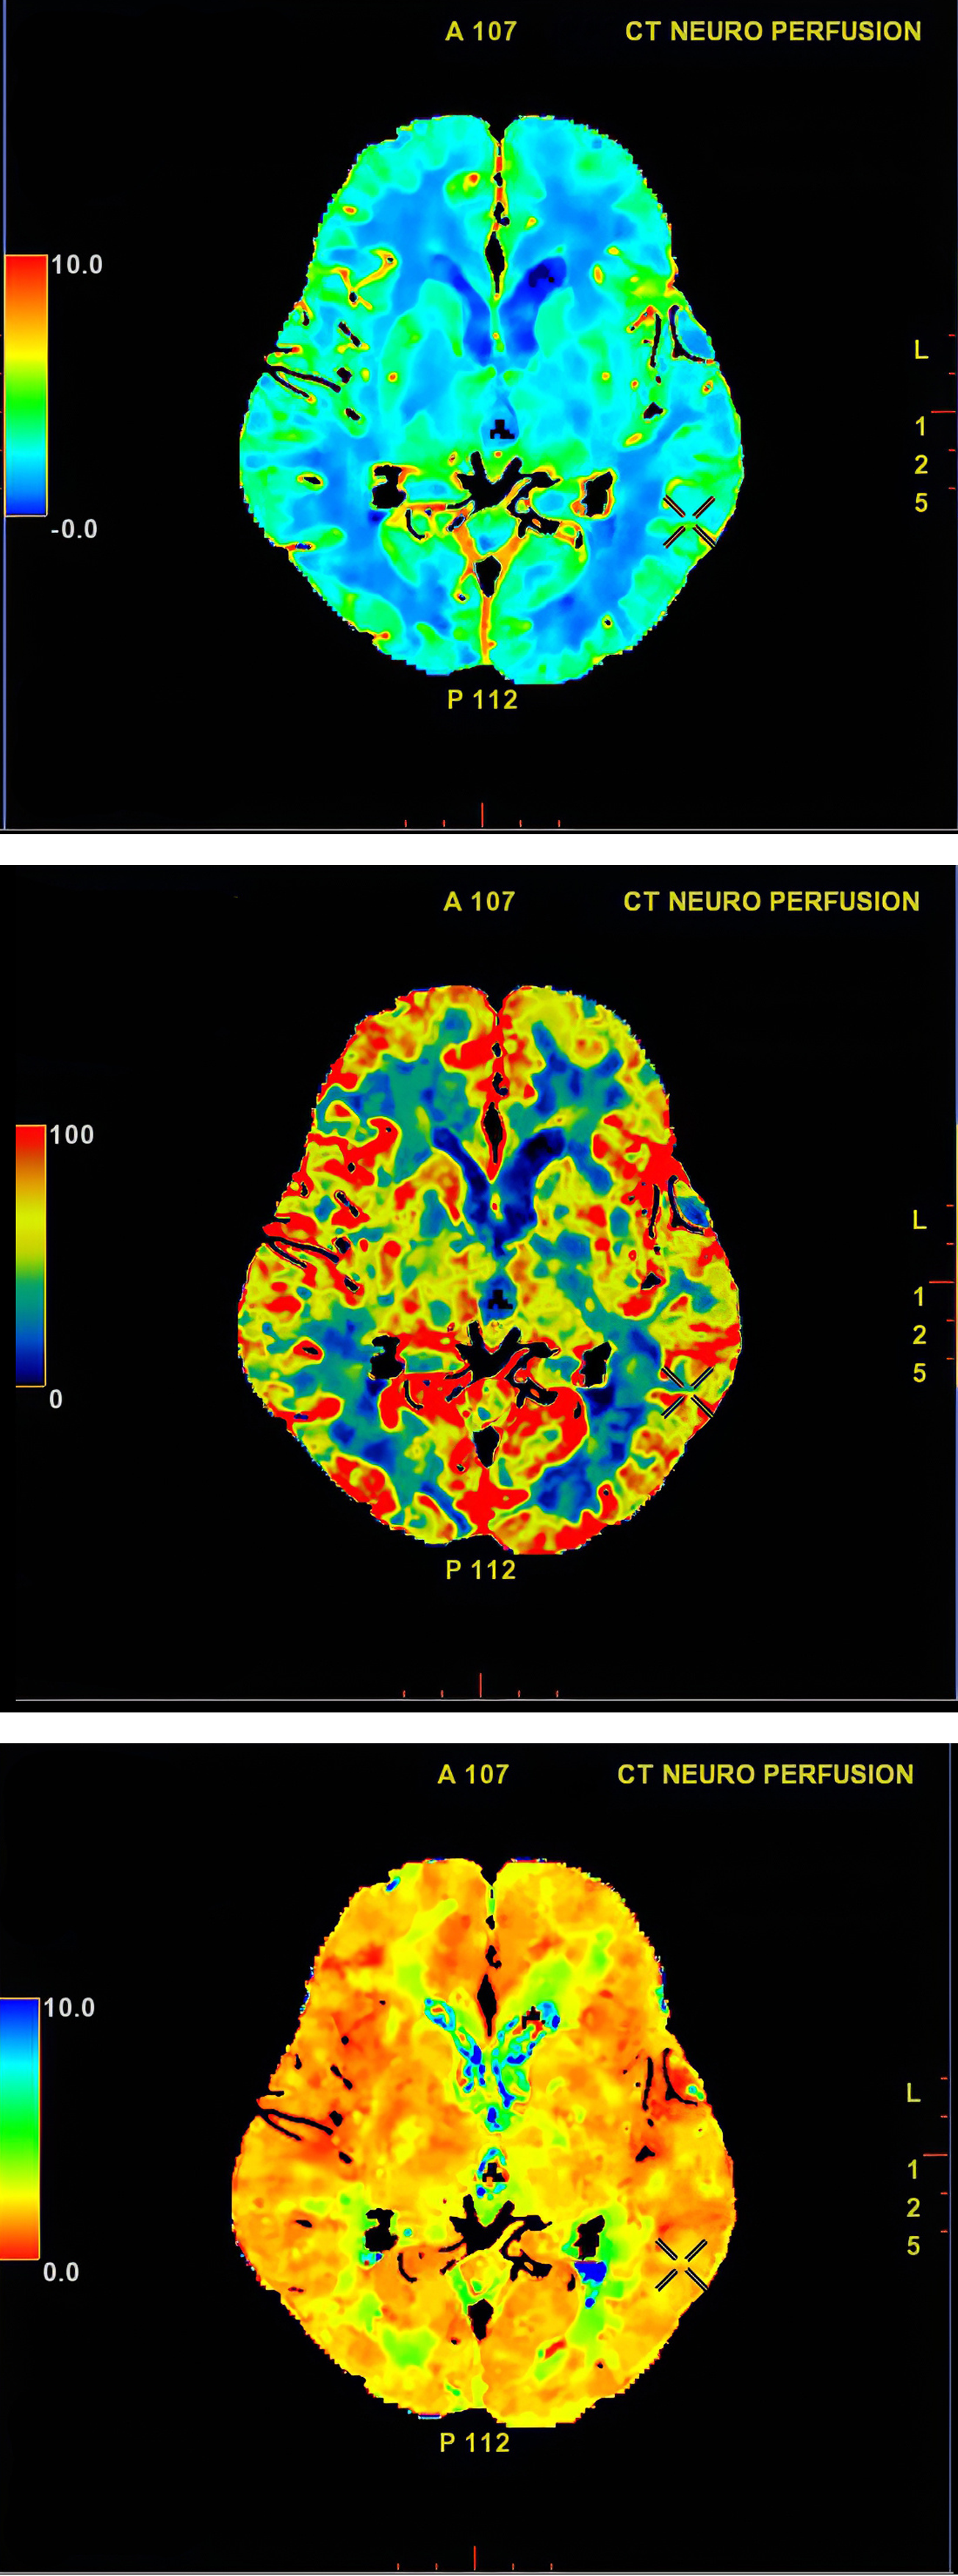

La neurociencia y la neurotecnología están en rápida evolución, logrando avances significativos que han facilitado una mejor comprensión del funcionamiento cerebral. Estos campos han dado lugar a nuevas tecnologías, como las avanzadas técnicas de imagen cerebral, que permiten a los científicos observar el cerebro en acción y entender cómo se procesa la información y se toman decisiones. A través de herramientas como la resonancia magnética funcional (fMRI), se han estudiado diversas enfermedades y trastornos, desde la depresión hasta el Alzheimer, ampliando notablemente el conocimiento en estas áreas.